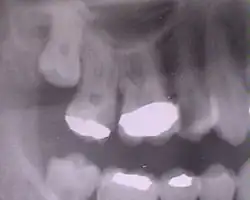

Zahnheilkunde

In der Zahnmedizin sind als solche Risikostellen hinsichtlich der Kariesentstehung zu nennen: Zahnfissur, Zwischenzahnfläche (approximal), Zahnhals, Foramen caecum dentis (Blindes Loch innen (palatinal) an den oberen Schneidezähnen) und Füllungs- und Kronenränder.